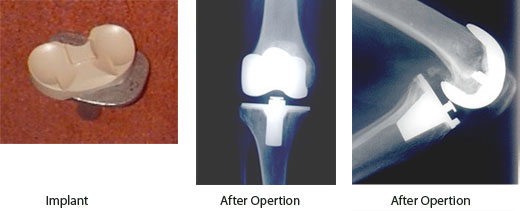

Alternatives to knee replacement surgery for elderly. Ad submit your research with journal of electrical and computer engineering. Warning signs that your knee replacement implants are loosened. The number of knee replacement surgeries performed increased 65 percent between 2000 and 2006, the agency for healthcare.

Anterior cruciate ligament (acl) reconstruction is similar to joint replacement and can now be done with various regional anesthesia techniques. This procedure is performed with all age group of people except children. One study of over 5000 people found that after two years, patients who underwent total knee replacement surgery improved their knee pain and function by 36% 24.